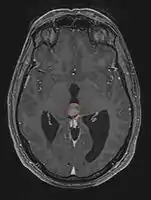

Pineal Gland Tumors

- Work-up includes MRI, CSF, serum markers for bHCG and AFP